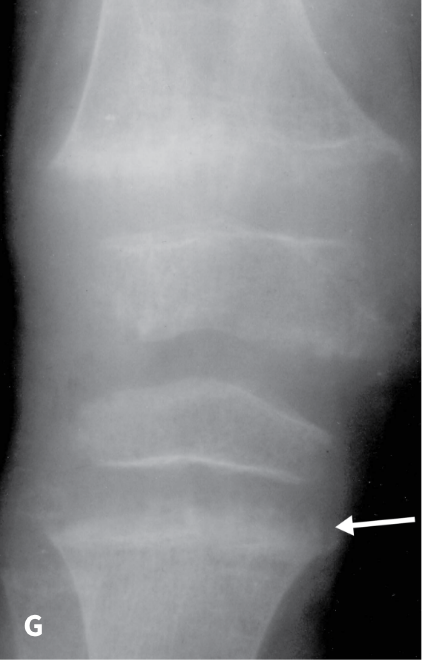

The RSS is a quantitative method that uses radiographs to assess the severity of rickets at the wrists and knees. Originally validated in nutritional rickets, the score is based on the degree of metaphyseal fraying, metaphyseal cupping, and the proportion of the growth plate that is affected. It is a 10-point scale, for which 10 represents the most severe radiographic changes due to rickets and 0 represents the absence of these changes.1

Although the severity and duration of rickets vary considerably between XLH and nutritional rickets, the radiographic features of rickets at the growth plate are similar in the two disorders, which allowed validation of the RSS in XLH. The RSS correlates with serum alkaline phosphatase (ALP) levels, a biochemical marker of rachitic activity, and this scoring system can be used to assess the radiographic response following treatment of nutritional or XLH rickets.

The RSS in XLH has been reported to range from 0 to 4.5; however, despite the smaller RSS range observed in XLH patients, inter- and intra-rater reliability are similar to those reported for nutritional rickets. Patients with XLH who had a baseline RSS ≥1.5 were shown to have more severe hypophosphatemic bone disease, including higher levels of alkaline phosphatase, and greater impairments in clinical outcomes compared with patients who had a baseline RSS <1.5.